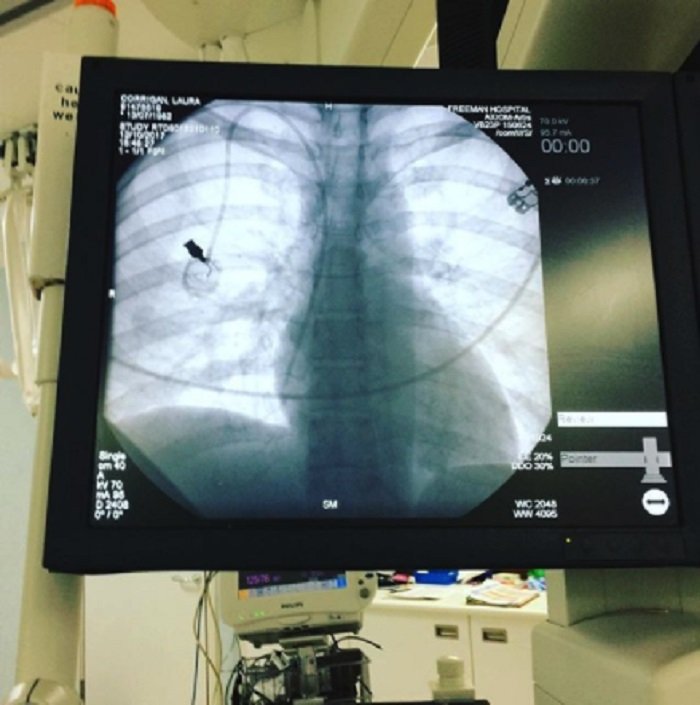

У женщины рак кишечника, который распространился и на легкие, поэтому она проходит курс химиотерапии. Кроме Макса, у Лауры есть еще полуторагодовалый сын Финн. Воспитывает мальчиков женщина сама.

36-летней женщине диагностировали рак в прошлом году после жалоб на боли в кишечнике и обнаружения крови в испражнениях.